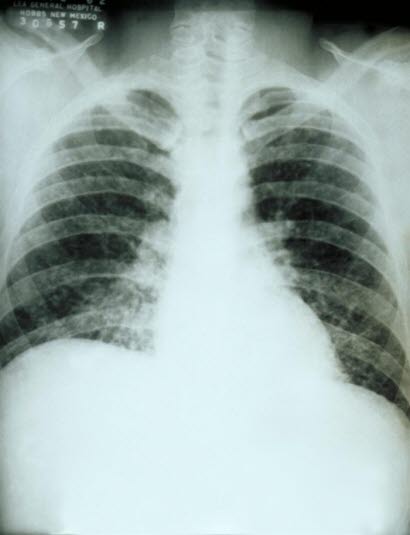

Opplysninger om reisemål, grottebesøk og luftveissymptomer kan gi mistanke om diagnosen. Blodprøver på antistoffer, eventuelt dyrkningsprøver fra luftveiene, kan bekrefte diagnosen. Røntgen-bilder av lungene kan vise typiske funn.